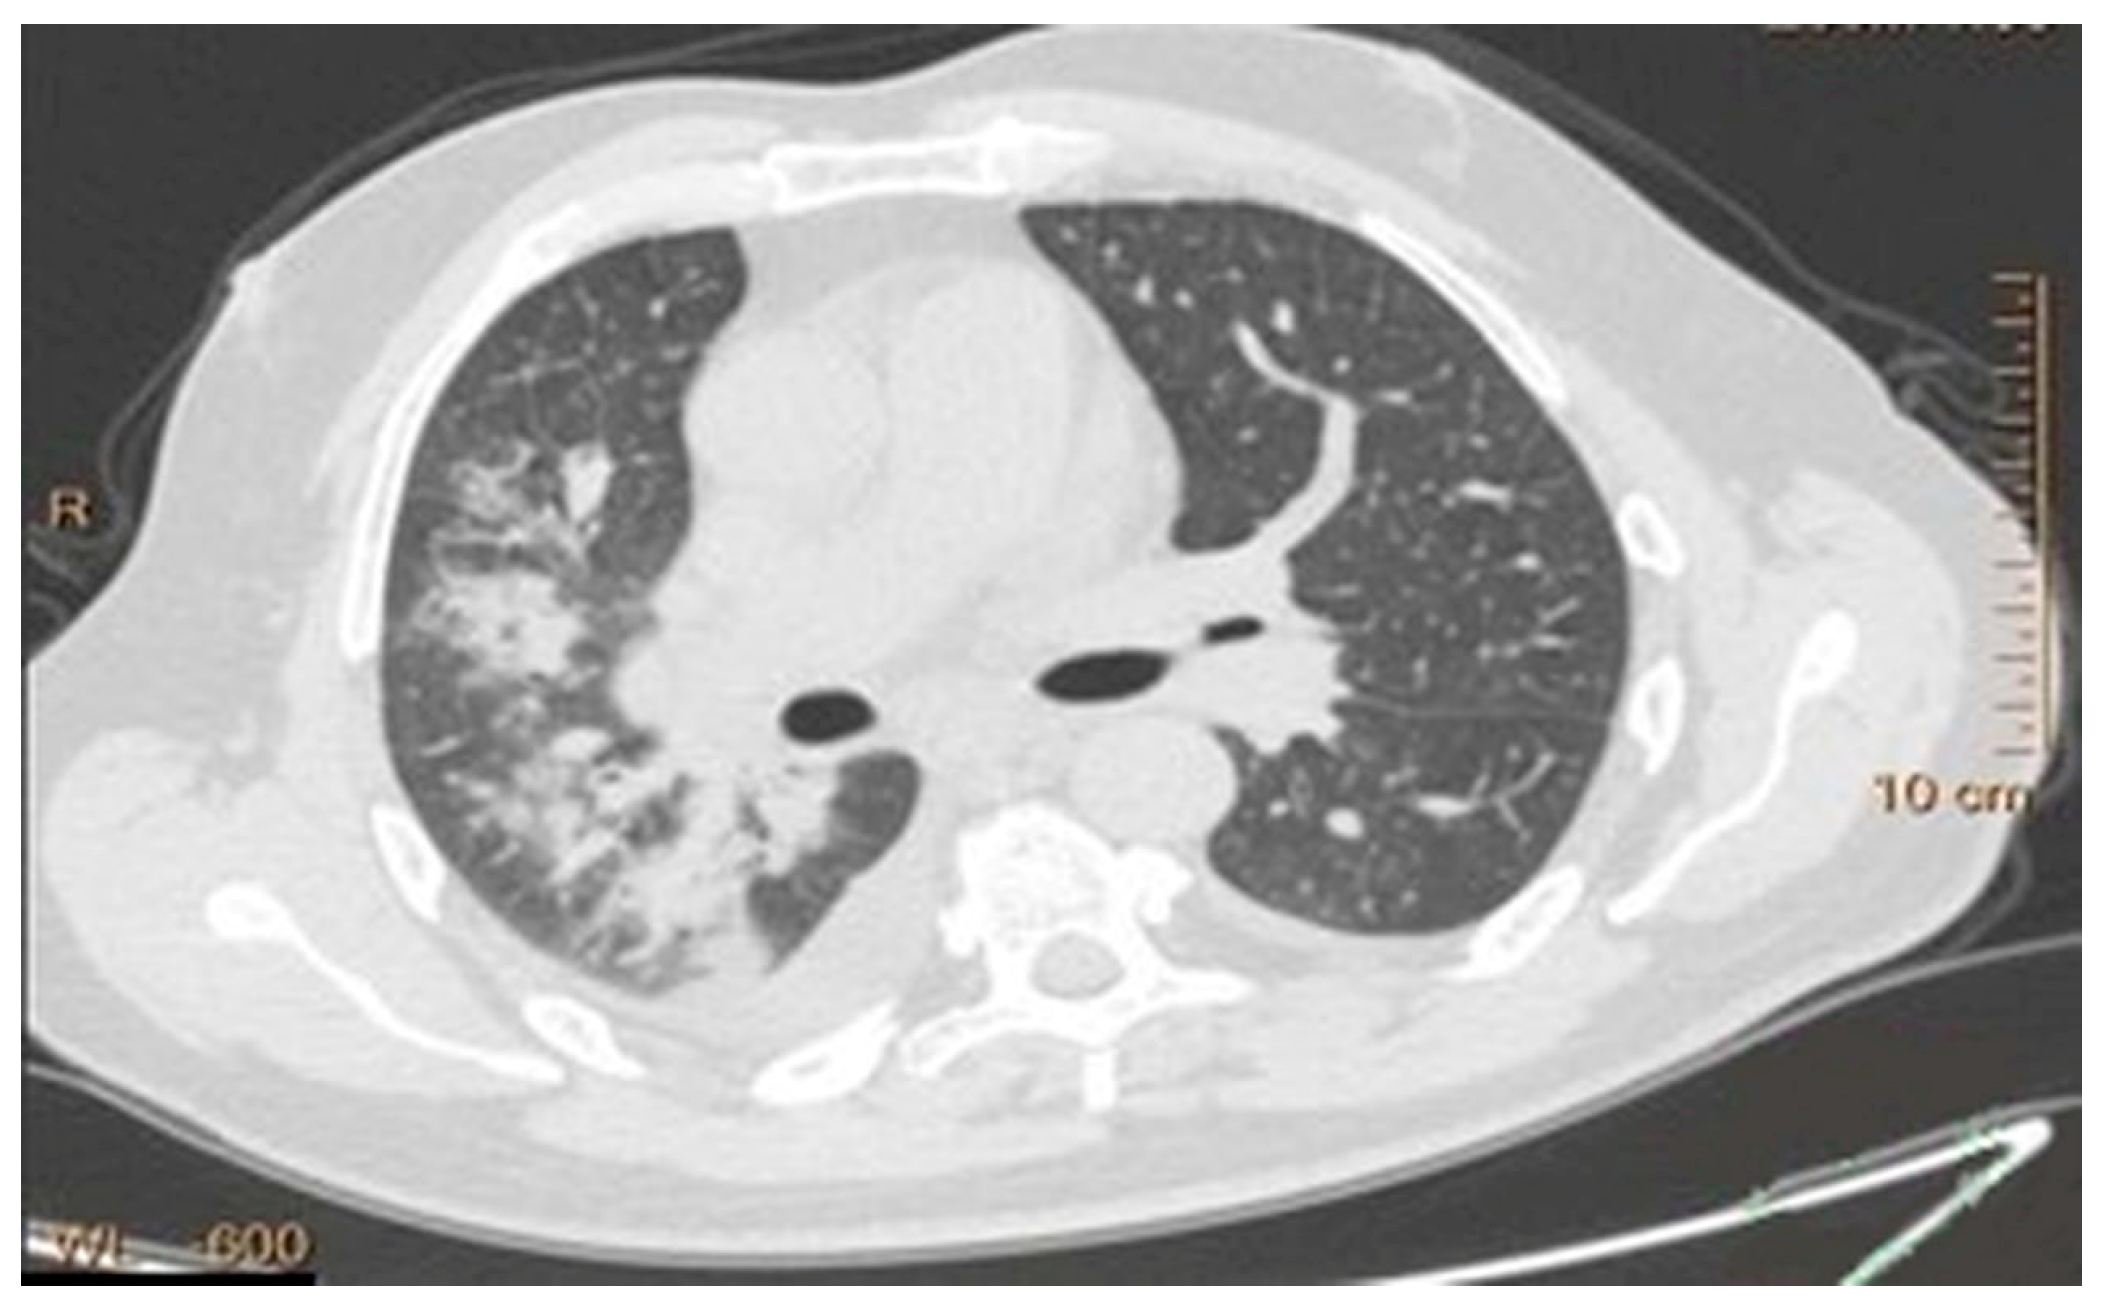

The Iraqi Lung Cancer Image Dataset (ILCID) utilized in this research was collected from three large Iraqi medical metropolitan centers, which were diverse and clinically reliable. The three hospitals are Oncology and Alternative Nuclear Medicine Hospital in Mosul (1500 images), Al-Zahrawi Special Hospital in Mosul (800 images), and Shilan Special Hospital in Duhok (700 images), whereby a total of 3000 high-resolution lung CT scan images were recorded according to ethical approval from the Iraqi Ministry of Health, Nineveh Health Directorate, Training and Human Development Center (Ethical ID Code: 2023118, approved in 7 June 2023). The collection of data started in October 2022 by obtaining formal permission from each institution. All scans were made with the Philips Brilliance barefoot CT Scanner (model 2019), where the image quality and the imaging parameters were standardized to ensure uniform recorded data. The dataset has a wide range of lung cancer manifestations, such as various tumor volumes, types, and phases of the disease (early, intermediate, and advanced). Each scan was annotated manually by expert radiologists who gave each scan accurate segmentation masks to enable powerful model training and assessments. Inclusion criteria were also very strict to make sure that it is clinically relevant and includes various types of cancer (small-cell and non-small-cell lung cancer) and diverse patient demographics to improve the generalization. Before developing the model, there was an extensive preprocessing pipeline that eliminated artifacts and low-quality scans and normalized image properties, leaving a high-quality dataset free of problems and ready to be used in advanced computer-aided diagnosis. Figure 5 shows samples of the collected dataset.

Figure 5. Samples of the collected dataset.